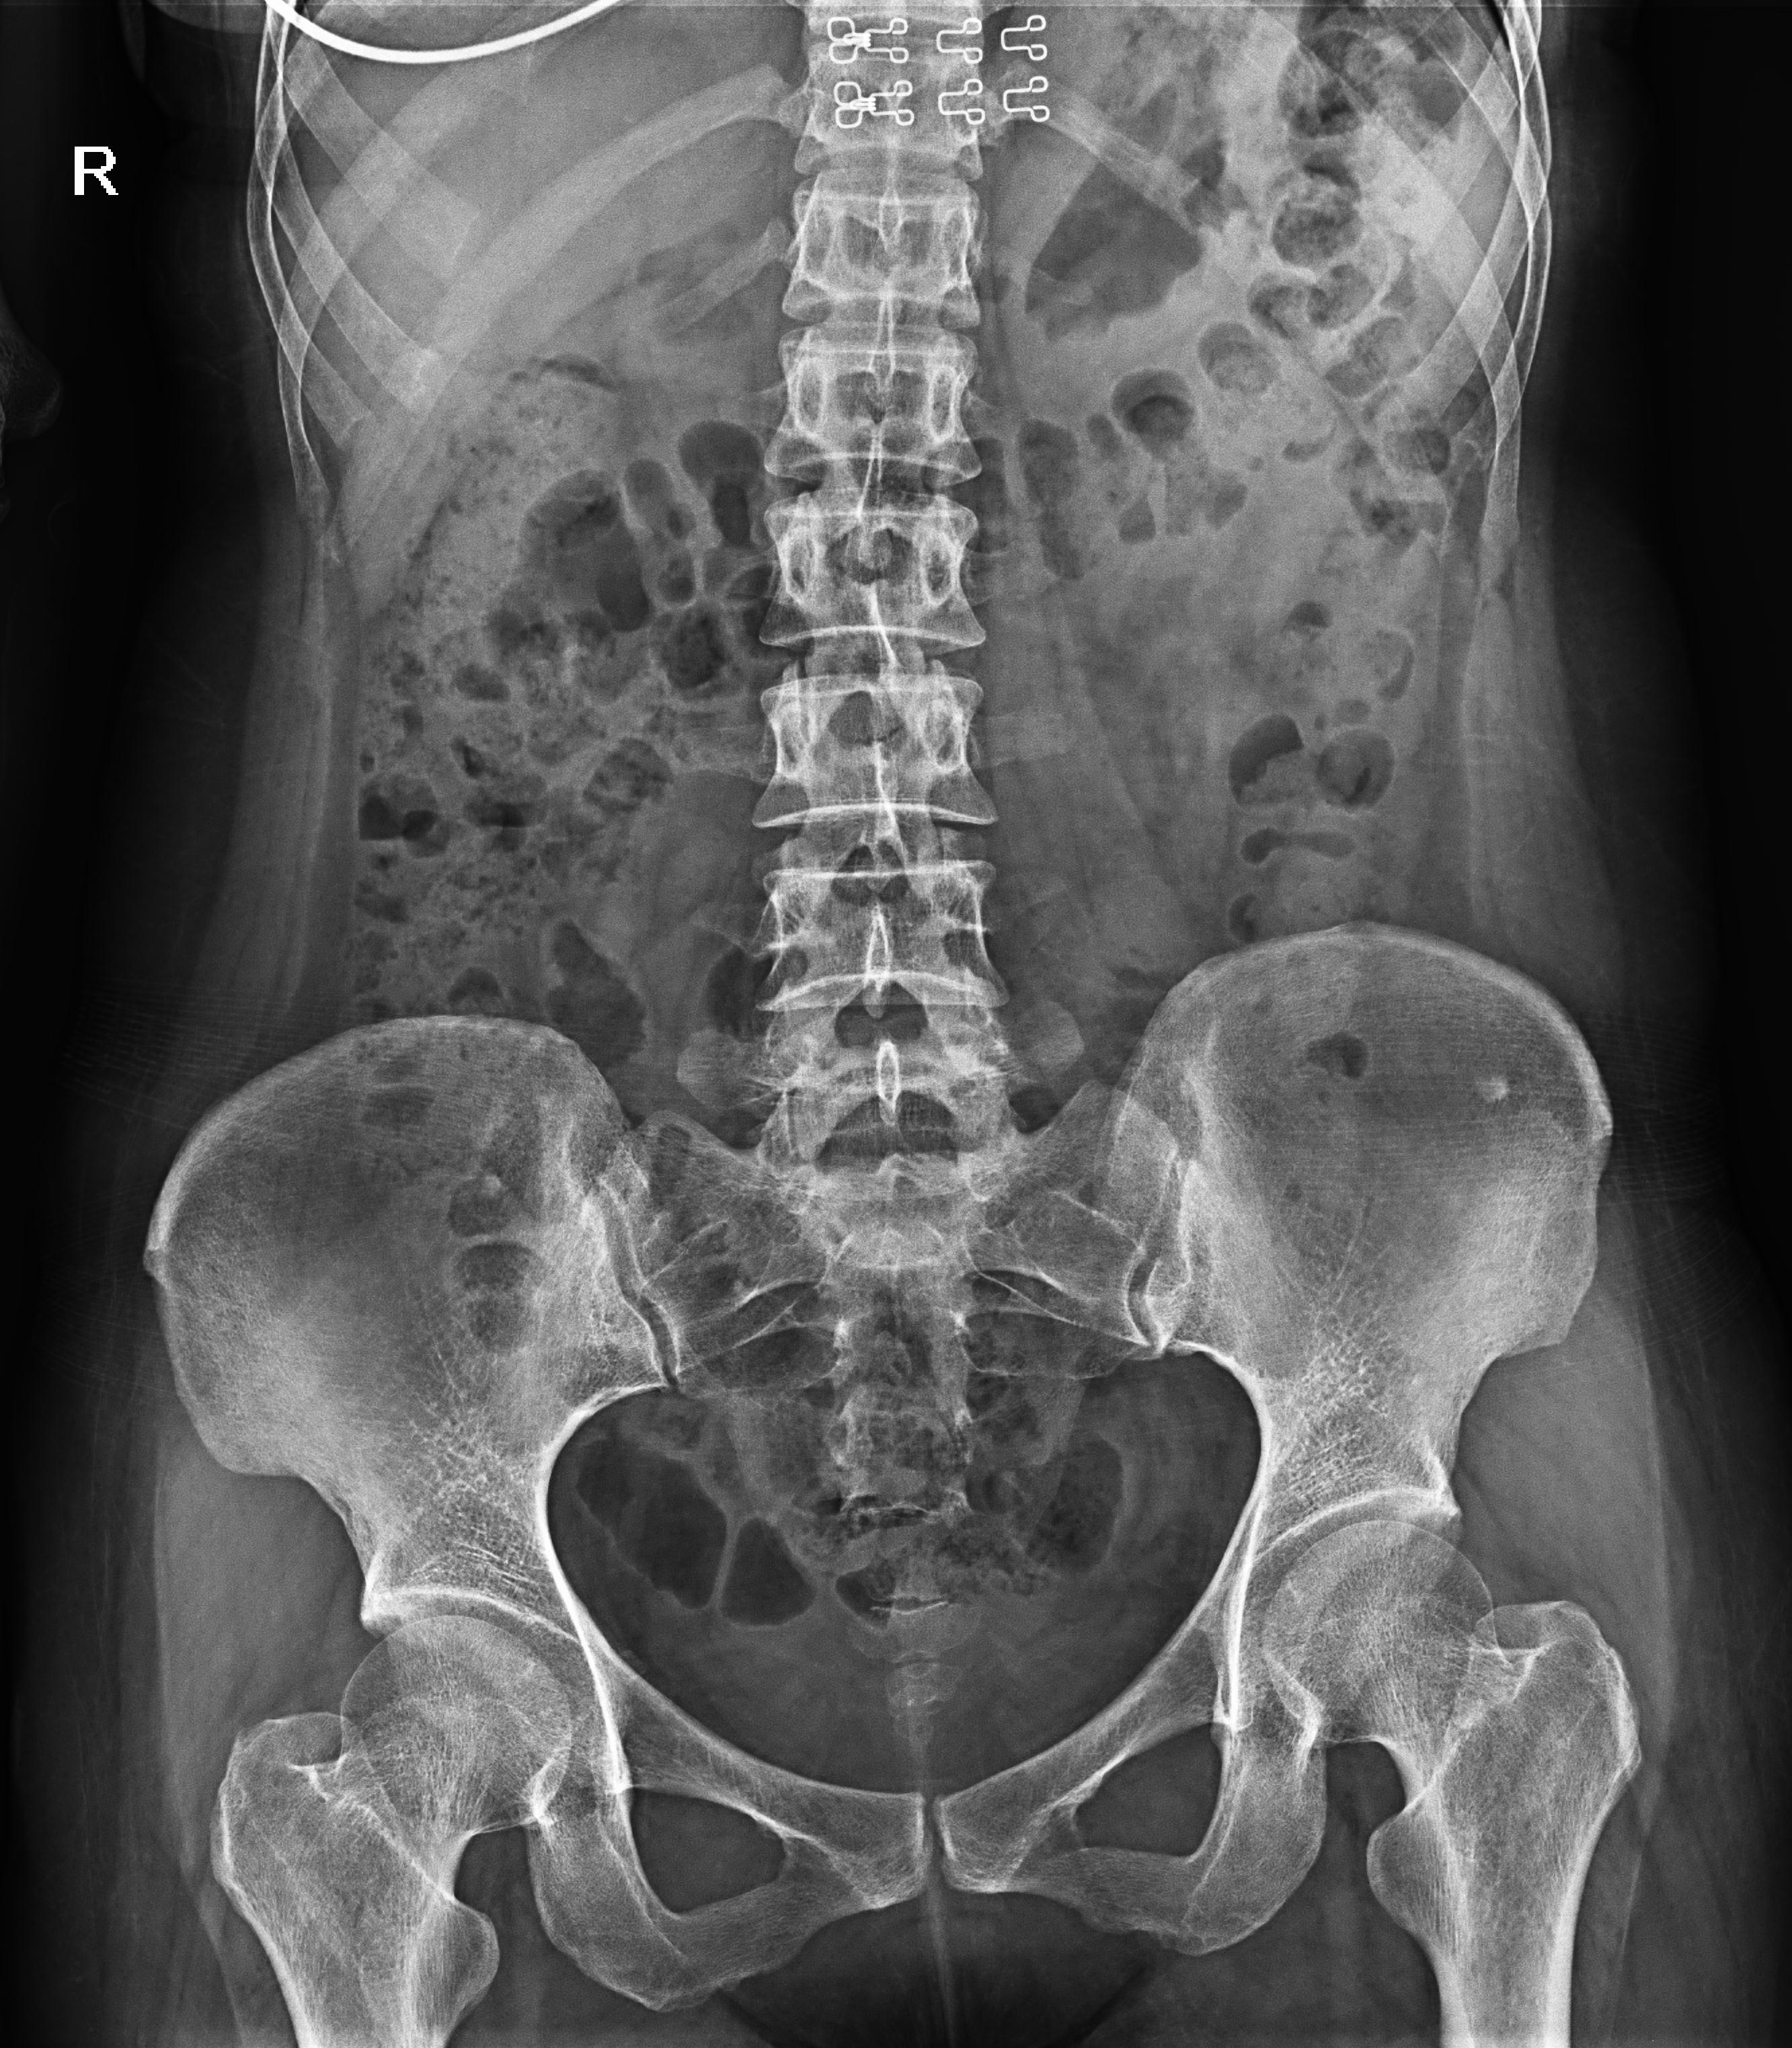

盆骨 (2)

腎盂造影